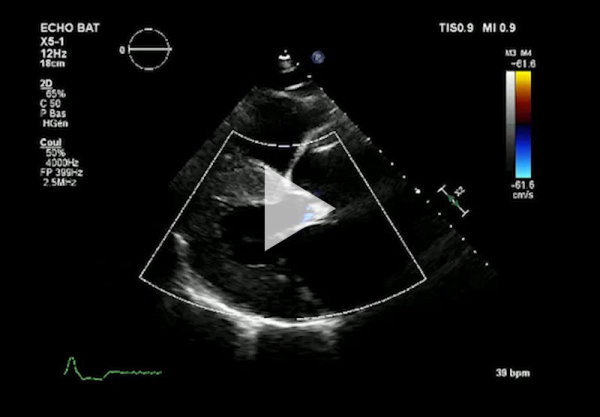

Vidéo 2 - Échocardiographie 2D en incidence parasternale grand axe couleur

- Ventricule gauche non dilaté, hypertrophie concentrique symétrique majeure non-obstructive, hypokinésie globale, aspect scintillant du myocarde

- FEVG 45- 50 %

- Pressions de remplissage VG probablement élevées

- Dilatation bi-atriale marquée (OG 54 ml/m²)

- Fuite mitrale centrale modérée, épaississement des valves

- Ventricule droit non dilaté modérément hypertrophique

- Fonction systolique VD diminuée

- Hypertension pulmonaire peu probable (Vmax IT 2,85 m/s)

- Décollement péricardique minime inférieur